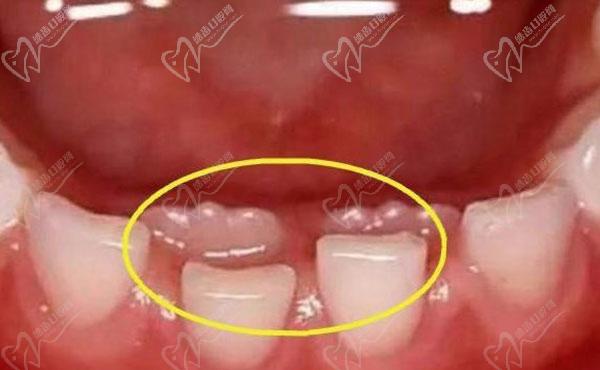

如果孩子的乳牙还没掉就开始长出新牙,可以说是相当正常的现象,一般医生会建议拔除,以免影响恒牙的发育。这种现象也被称为双排牙,多见于6-8岁的儿童。双排牙常见于下门牙和上门牙,虽然在不同孩子身上的具体表现可能有所不同,但通常情况下新牙会衔在乳牙上面或者横在乳牙后面。这种情况不需要特别处理,大部分情况下在相应的时间里新牙会自动将乳牙推出,然后正常地占据位置。然而,在特殊情况下,如果牙齿未能正常替换,建议咨询口腔医生的建议。

双排牙是指孩子的新牙在乳牙还未脱落的情况下生长出来,导致两排牙齿同时存在的情况。这对家长来说可能会引发一些担忧,担心孩子的牙齿排列会受到影响。当家长带孩子去看牙医时,有时候医生会建议拔除其中一颗新牙,以帮助后来的新牙找到正确的位置。然而,很多家长会好奇,拔掉双排牙后,剩下的新牙是否能自动归位。